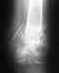

Застарелый вывих ключицы. Какой тип фиксации выбрать и нужна ли пластика? В середине апреля этого года получил травму плечевого сустава, вывих акромиального конца левой ключицы. Около месяца рука беспокоила, были боли. Потом боли прошли и остался дискомфорт в районе ключицы, она выпирала вверх, ограничений в движении не было. В июле была проведена операция, открытое вправление вывиха акромиального конца ключицы, произведена пластика связок капроновым шнуром с фиксацией двумя спицами и повязкой дезо на шесть недель. Недавно был на приёме у травматолога, подвывих сохраняется, наблюдается выпячивание ключицы и эффект клавиши при нажатии на неё, неприятные ощущения и щелчки при движении рукой. Врач рекомендует фиксацию крючковидной пластиной без пластики связок. Нужно ли делать пластику ключично-клювовидной связки? Какой тип фиксации лучше выбрать в моём случае? Снимок после первой операции прилагаю.